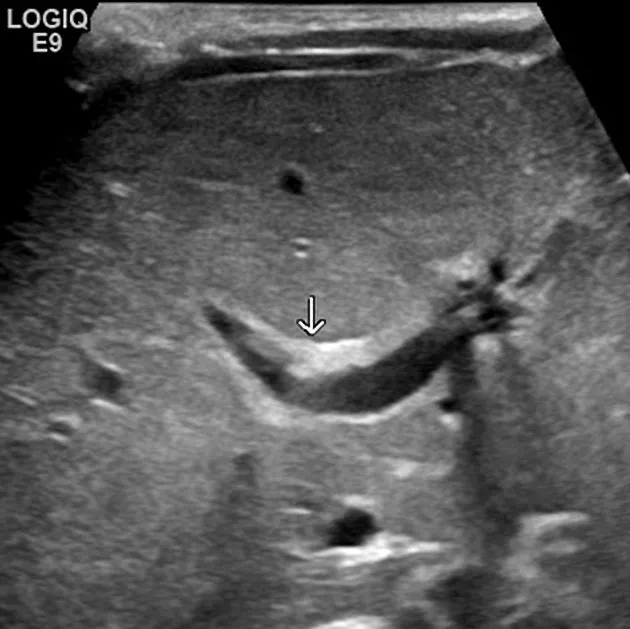

- Key: Triangular Cord (TC) sign (>4mm), absent/small gallbladder.

-

⭐ The 'triangular cord sign' on ultrasound (echogenic fibrous tissue anterior to portal vein) is highly suggestive of Biliary Atresia.